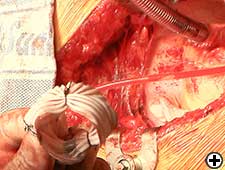

- Cross clamp, cardioplegia, aortotomy, and excision of aortic valve as routine.

- Divide aorta by extending aortotomy.

- Dissect under surface of aorta: proximally to the root and distally to the under surface of arch.

- Replace aortic valve as per routine.

- Distal part of aorta passed back through the folded Dacron graft.

- Aorta re-anastomosed with 4.0 continuous sutures.